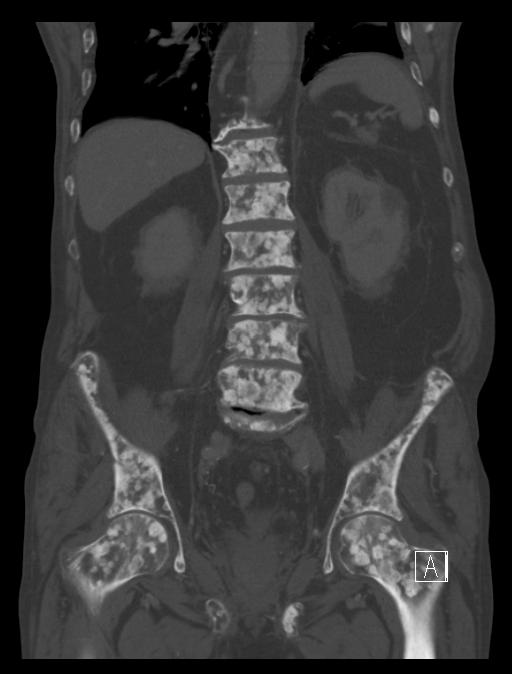

- Kidney stones